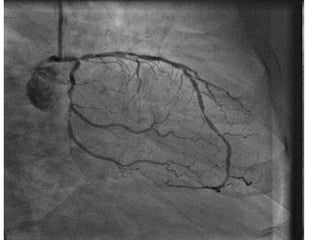

A 49-year-old male presented with syncope and was found to have cardiomyopathy with severely reduced ejection fraction less than 25% based on echocardiogram findings. Cardiac catheterization showed severe blockages of the left anterior descending and circumflex arteries. Despite a non-ischemic etiology, the patient was evaluated for an implantable cardioverter-defibrillator due to the reduced ejection fraction. A separate 33-year-old male presented with chest pain and was diagnosed with an anterior STEMI based on ECG findings.